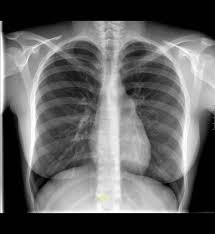

Neumotórax

Se define al neumotórax como la presencia de aire

en la cavidad pleural el que proviene producto de una lesión en el parénquima

pulmonar, lo que con lleva un colapso de este parénquima en mayor o menor grado

según sea la cuantía del neumotórax.

Los neumotórax pueden ser clasificados según su

causa y forma de presentación. Ellos pueden ser catalogados como:

Espontáneos (primarios o secundarios)

Traumáticos (Abiertos o cerrados)

Iatrogénicos.

Los espontáneos primarios se ven en aquellos

pacientes sin antecedentes pulmonares, y una vez que se reexpande el pulmón,

éste no presenta ninguna anormalidad en la Rx. de tórax. Los espontáneos

secundarios son aquellos en los cuales el neumotórax se debe como complicación

de una enfermedad preexistente a nivel de parénquima pulmonar. Los traumáticos

pueden verse en relación a traumatismo cerrado o abierto y en estos últimos se

distinguen los por arma blanca y los por arma de fuego. Los iatrogénicos a su

vez se relacionan frecuentemente a la instalación de vías venosas centrales o a

toracocentesis ya sea con fines diagnósticos o terapéuticos.